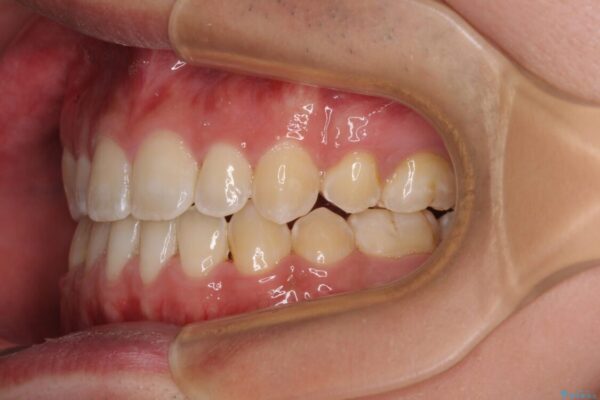

治療途中

• 口元の突出感を改善 受け口傾向の咬み合わせの抜歯矯正 治療途中画像